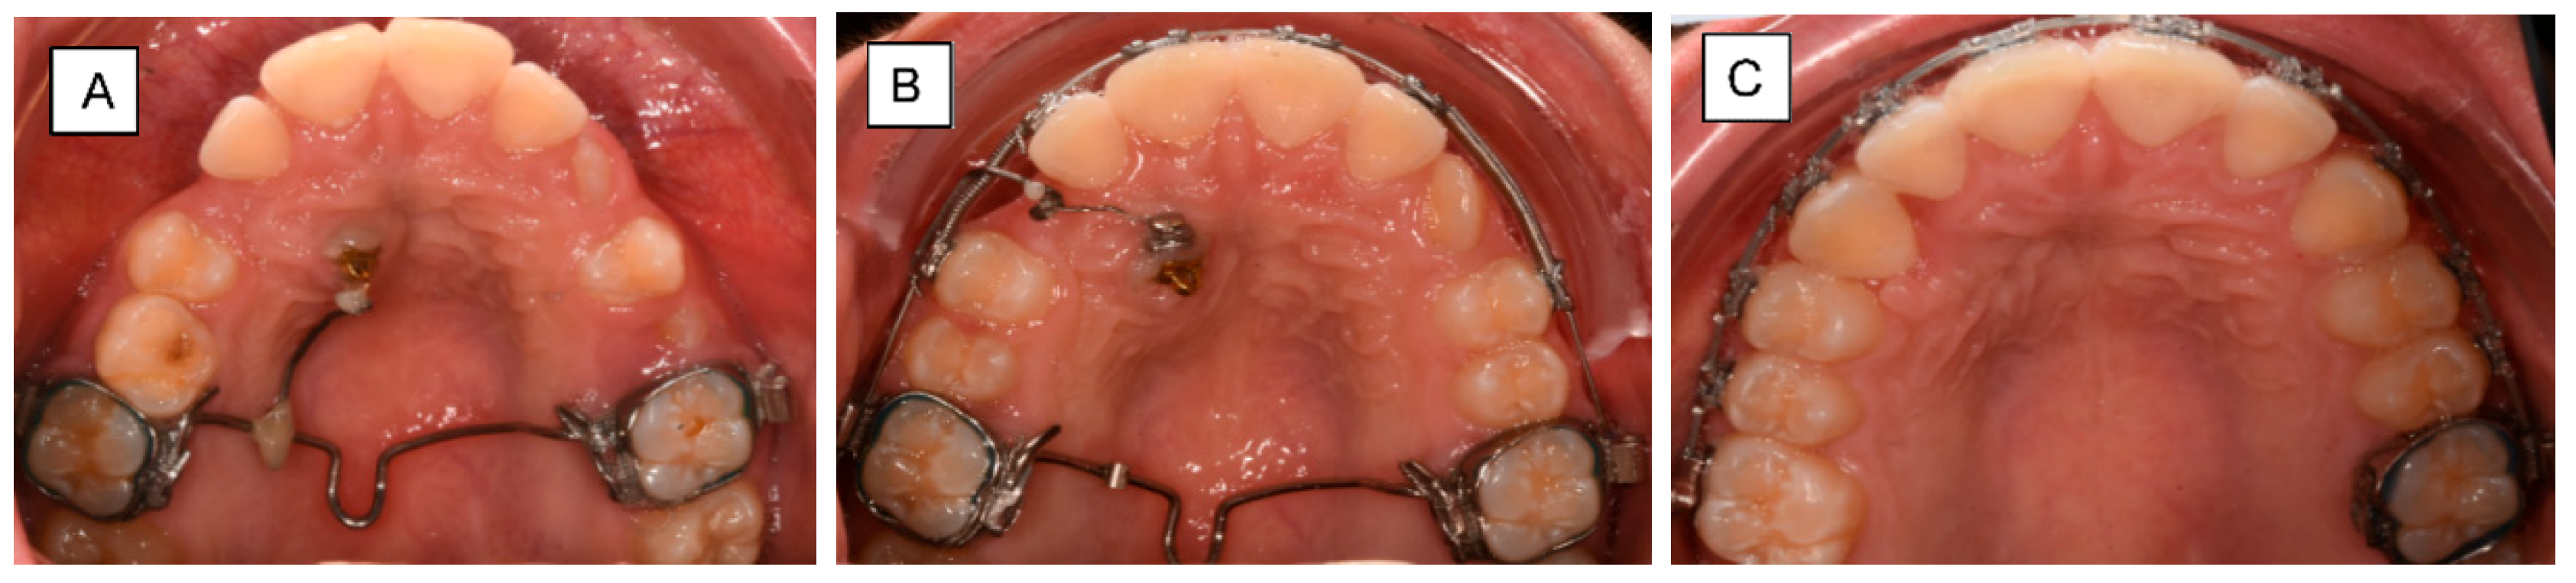

2. Anchorage Considerations

3. Impacted Teeth

3.1. Buccal Impaction

3.2. Palatal Impaction